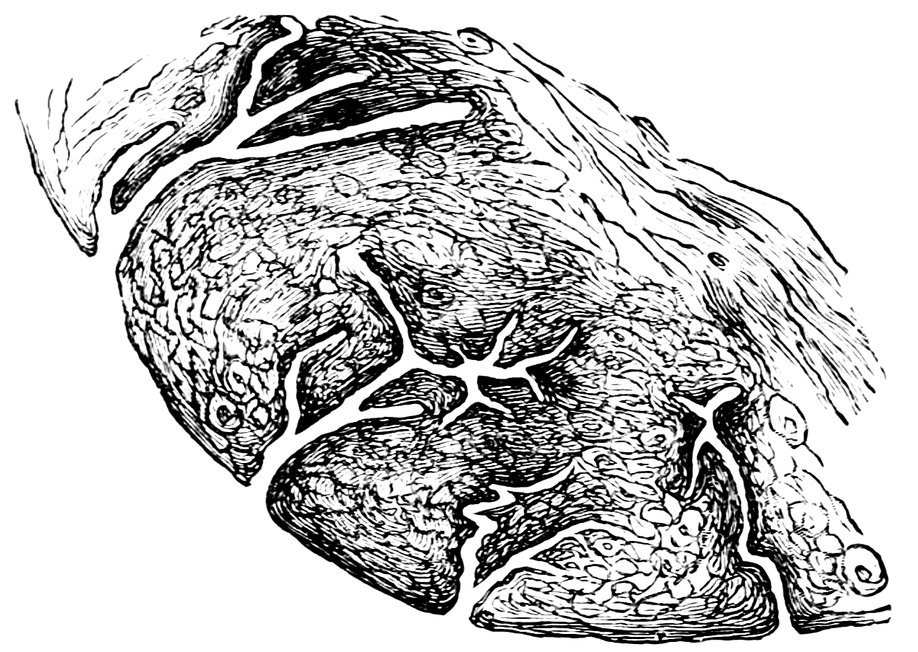

| 84. | Sagittal section through the ovary of a girl aged sixteen | 583 |

| 85. | Sagittal section through the ovary of a woman aged seventy-two years | 584 |

| 86. | Diagrammatic Representation of the Graafian Follicle | 585 |

| 87. | Ovary of a Girl aged nineteen years (Normal Size) | 585 |

| 88. | Ovary of a Woman seventy-two years of age (Normal Size) | 585 |

| 89. | 586 | |

| 90. | 587 | |